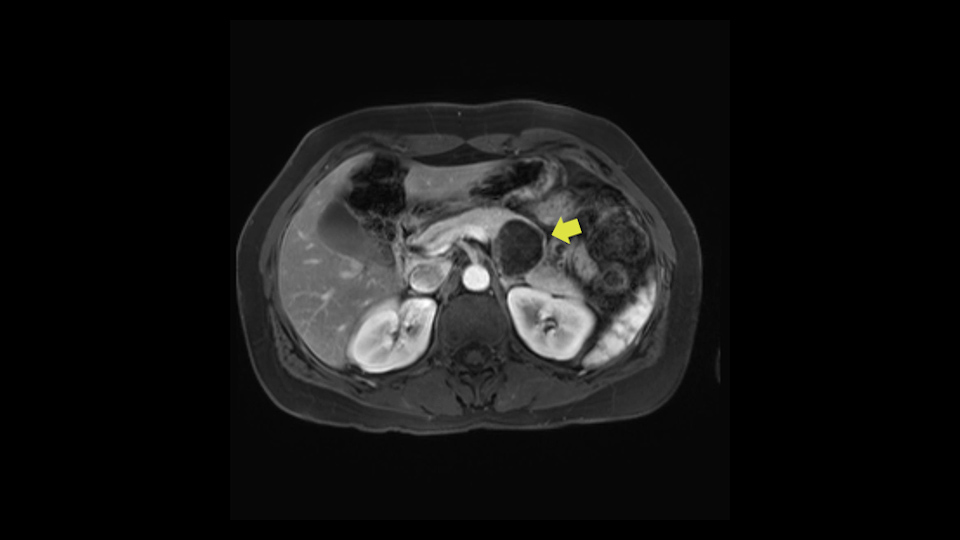

The lesion itself is quite adjacent to and abuts the splenic vein and therefore we need to anticipate that these two structures will be intimately related and possibly impossible to separate between the two.

The second slowing down moment or consideration I give to a distal pancreatectomy is the anatomy of the portal vein and the splenic artery. And so I look here and the anatomy is pretty straightforward. The splenic vein comes off normally and runs behind the pancreas and I can see the artery superior to that, again coming off in a normal manner from the celiac axis. So those two things, the portal vein and the splenic artery will be taken normally in this procedure.

So first step that we do: mobilize the splenic flexure first to visualize Gerota’s fascia and that would help bring down the colon and expose the pancreatic tail. So now that the pancreas is visible, division of the gastrocolic ligament will come into view. And a window can be created at the inferior edge of the pancreas to slowly lift the inferior edge to expose the splenic vein behind. This is the slow-down moment that I am talking about because the MR shows that there could be contact with the cyst. It’s important to know that to avoid perforation, to avoid rupture of the cyst, because we need to avoid touching the cyst, it is quite a size of 4.3 about 4cm.

I think the splenic vein, once I have slowly teased it off from the cyst and from the retropancreatic parenchyma, I would put a vessel loop around it to serve as a traction. So once you have the vessel loop or probably umbilical tape, to retract or pull the pancreatic parenchyma while we slowly tease it off and try to move superiorly to be able to expose the splenic artery. That is again another slow-down moment because sometimes we think that it is the splenic artery at the superior edge of the pancreas, but it could also be the hepatic artery as it branches from the celiac artery.